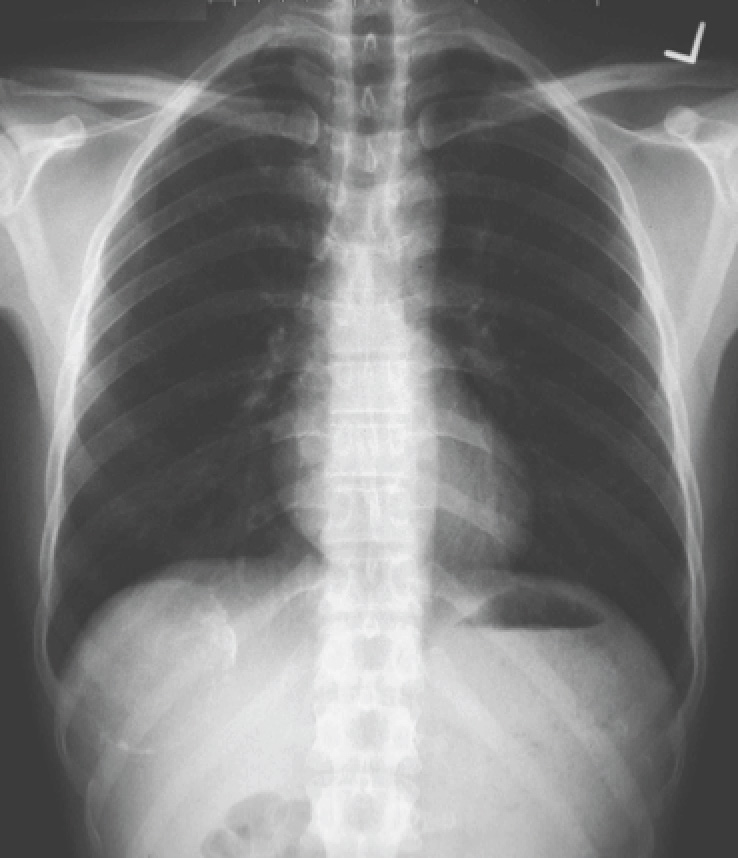

A man in late middle-age, who in his youth had traveled extensively around the region, presented with nagging right upper abdominal discomfort for 2 weeks. He had no fever. The chest X-ray is shown below.

There is a calcified cyst just below the right hemi-diaphragm. Given the location of the lesion, the question of an infectious disease, and the scope of the patient’s travels, it is likely to be a hydatid cyst. The corresponding CT image is shown below.

X Ray showing calcified margin of a cyst within liver. It might be Hydatid cyst of liver.